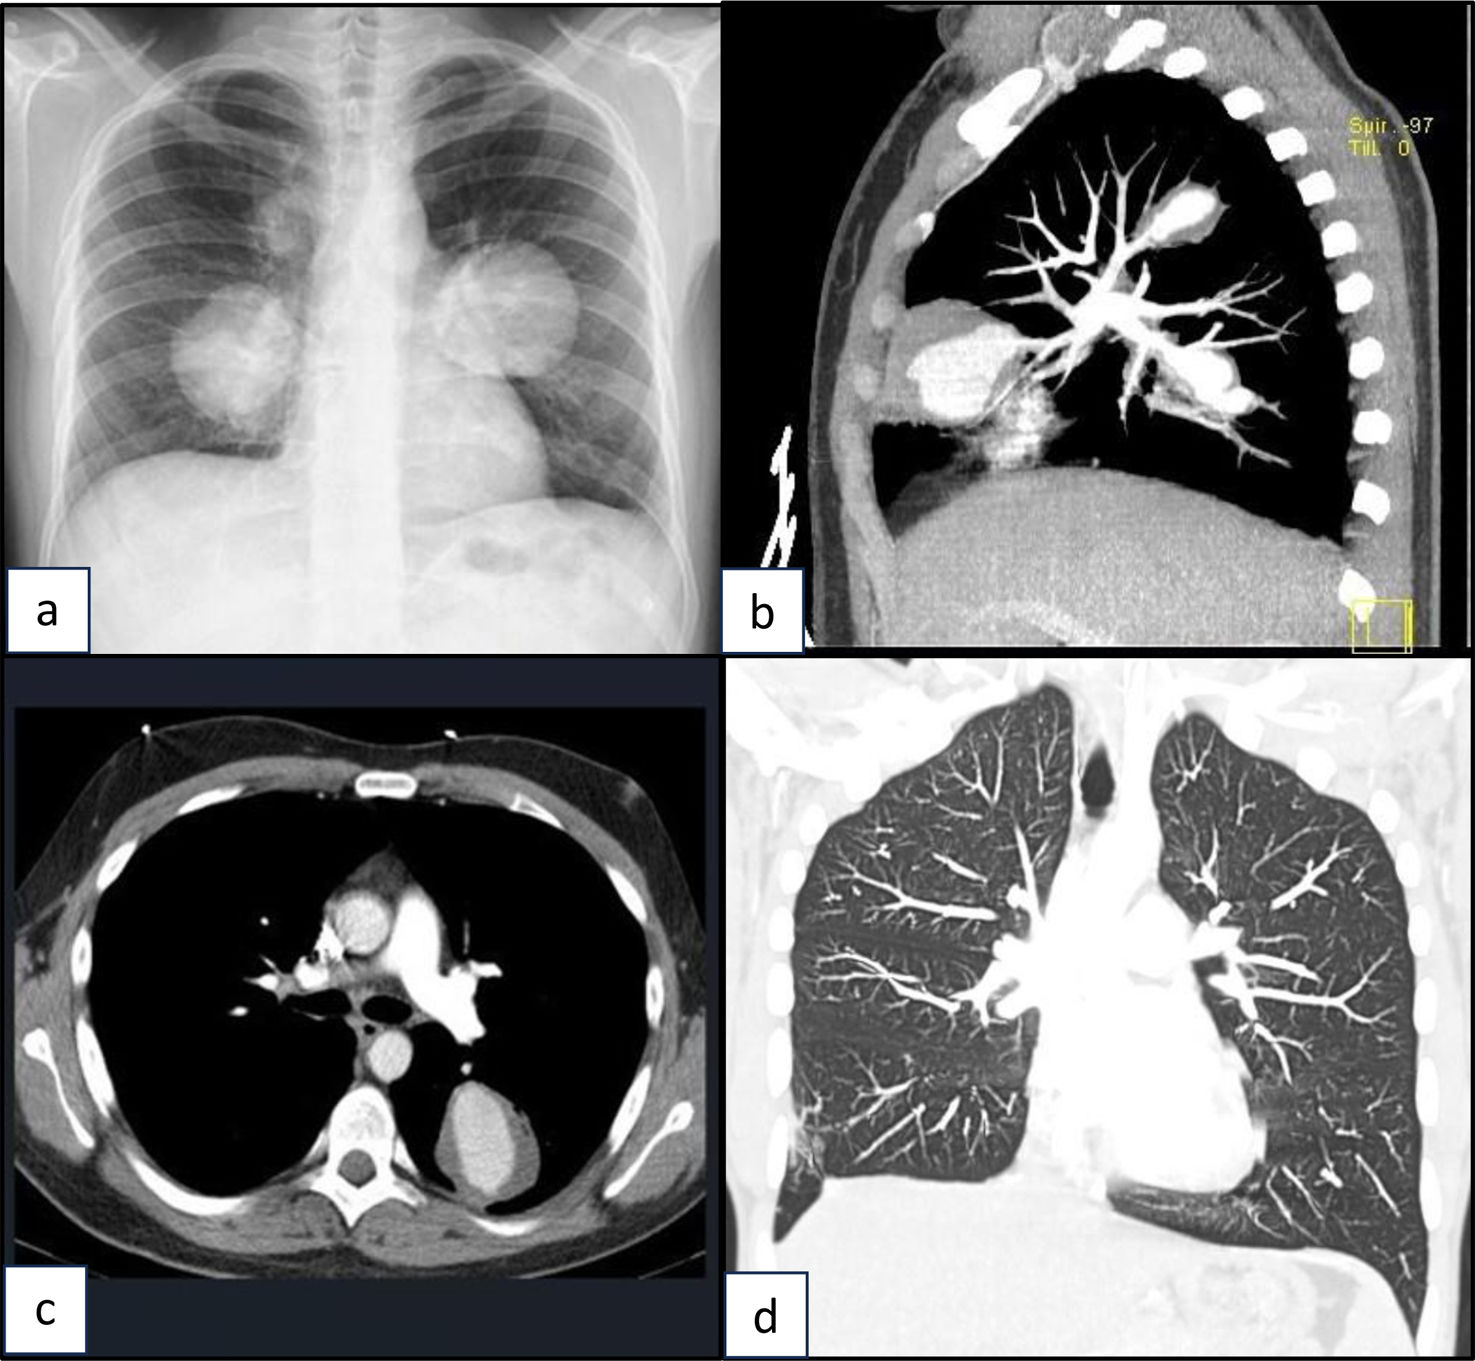

Open Respiratory Archives Hemoptysis in a Young Man with Behçet’s Disease

Hemoptysis in a Young Man with Behçet’s Disease